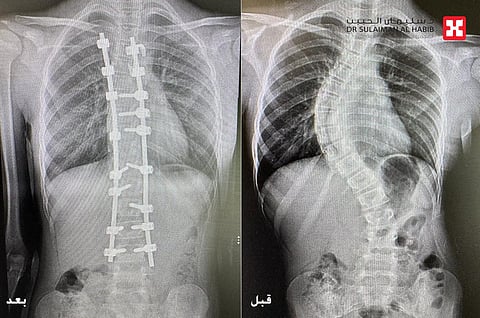

تمكن مستشفى الدكتور سليمان الحبيب بالعليا، من إنهاء معاناة فتاه تبلغ من العمر "13" عاما، مع الجنف من النوع النشط والمتطور بالعمود الفقري ، ونجح الفريق الطبي بقيادة الدكتور واصف السباعي استشاري جراحة العظام والعمود الفقري الحاصل على الزمالة البريطانية رئيس الفريق الطبي المعالج، في إجراء عملية معقدة استمرت 6 ساعات، تم خلالها تقويم العمود الفقري وتثبيت ودمج الفقرات بدون أية مضاعفات.

مفيداً بأنها خضعت لمجموعة من الفحوصات بأشعة بالرنين المغناطيسي (M.R.I)، بالإضافة إلى التحاليل المخبرية، والتي بينت إصابتها بحالة انحراف "جنف" مضاعف بالفقرات الصدرية والقطنية، وعدم القدرة على الإنحناء على الأرض، وعقب دراسة الفريق الطبي لحالته، وعلى ضوء نتائج الفحوصات والتحاليل، تم إخضاعها لعملية جراحية، تم فيها تقويم العمود الفقري بنسبة 94% وتثبيت ودمج الفقرات، بجهاز مراقبة الأعصاب أثناء الجراحة " Nerve Conduction Monitoring and Somatosensory Evoked Potential" للتاكد من سلامتها والعمل الوظيفي لها، بالإضافة إلى جهاز الملاحة العصبية، الأمر الذي ساهم في انجاح العملية.

وقال الدكتور واصف أن المريضة نومت بالمستشفى لمدة 5 أيام، واستطاعت المشي خلال 24 ساعة فقط من العملية، مع استعادتها القدرة على السير بتوازن، فضلاً عن القوام والمظهر الطبيعي لاستواء طول الكتفين أثناء المشي، وأصبح بإمكانها الاستلقاء والنوم على ظهرها، وقد خرجت من المستشفى في اليوم الخامس وهي بصحة جيدة، كما تمت متابعتها في العيادة وفق جدول الزيارات ما بعد العملية ، وتبين تحسنها وعودتها لممارسة حياتها بصورة طبيعية.